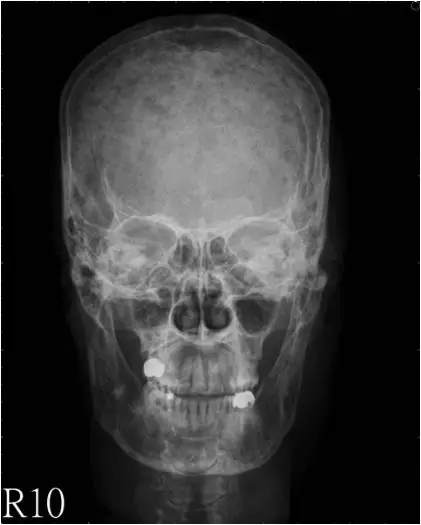

本題提供兩張頭顱 X 光片(正面 AP view 與側面 Lateral view):

正面觀(AP view): 顱骨全域可見多發性、小型、邊緣清楚的圓形透亮病灶(lytic lesions),分布於頂骨(parietal bone)及額骨(frontal bone)等處。這些病灶外觀如同「打孔」般(punched-out appearance),無硬化邊緣,為典型的溶骨性破壞,不伴有骨膜反應(periosteal reaction)。